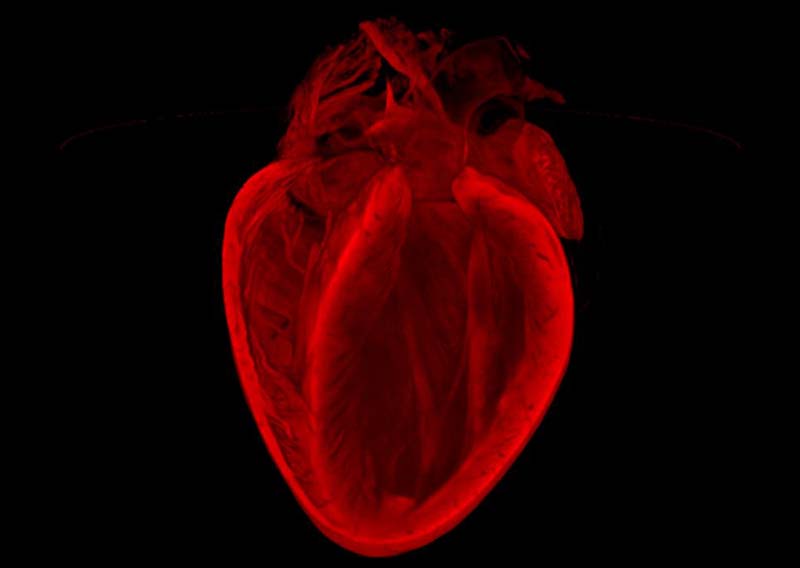

老鼠心臟醫(yī)學圖像變身絕美藝術品【圖】